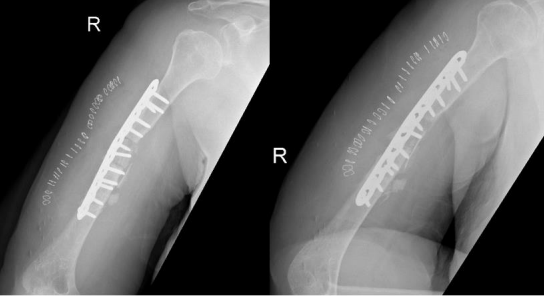

We present a case of recalcitrant humeral shaft nonunion in a 55-year-old obese female with type II diabetes, hypertension, and dyslipidemia. She sustained a rt humeral fracture in September 2017 and was treated at other facility with regular with 3.5 LC-DCP using 2 lag, 2 cortical, 6 locking , and 23 June 2018, she presented to the emergency after hearing a sudden pop associated with severe pain while performing daily activity with no significant trauma. Clinical examination revealed a healed surgical scar on the lateral aspect of the right arm, tenderness on palpation over the mid portion of the right arm, limitation of movement of the right shoulder and elbow due to pain, and intact distal pulses with no neurological deficits. Imaging in the form of X-rays revealed non-united right humeral shaft fracture. The fracture edges were smooth and partly sclerotic, with failure of a 3.5 mm locking compression plate was present in the form of plate fracture and screw pull-out at the level of the fracture (Figure 1). Laboratory investigations were negative for infection.

Figure 01